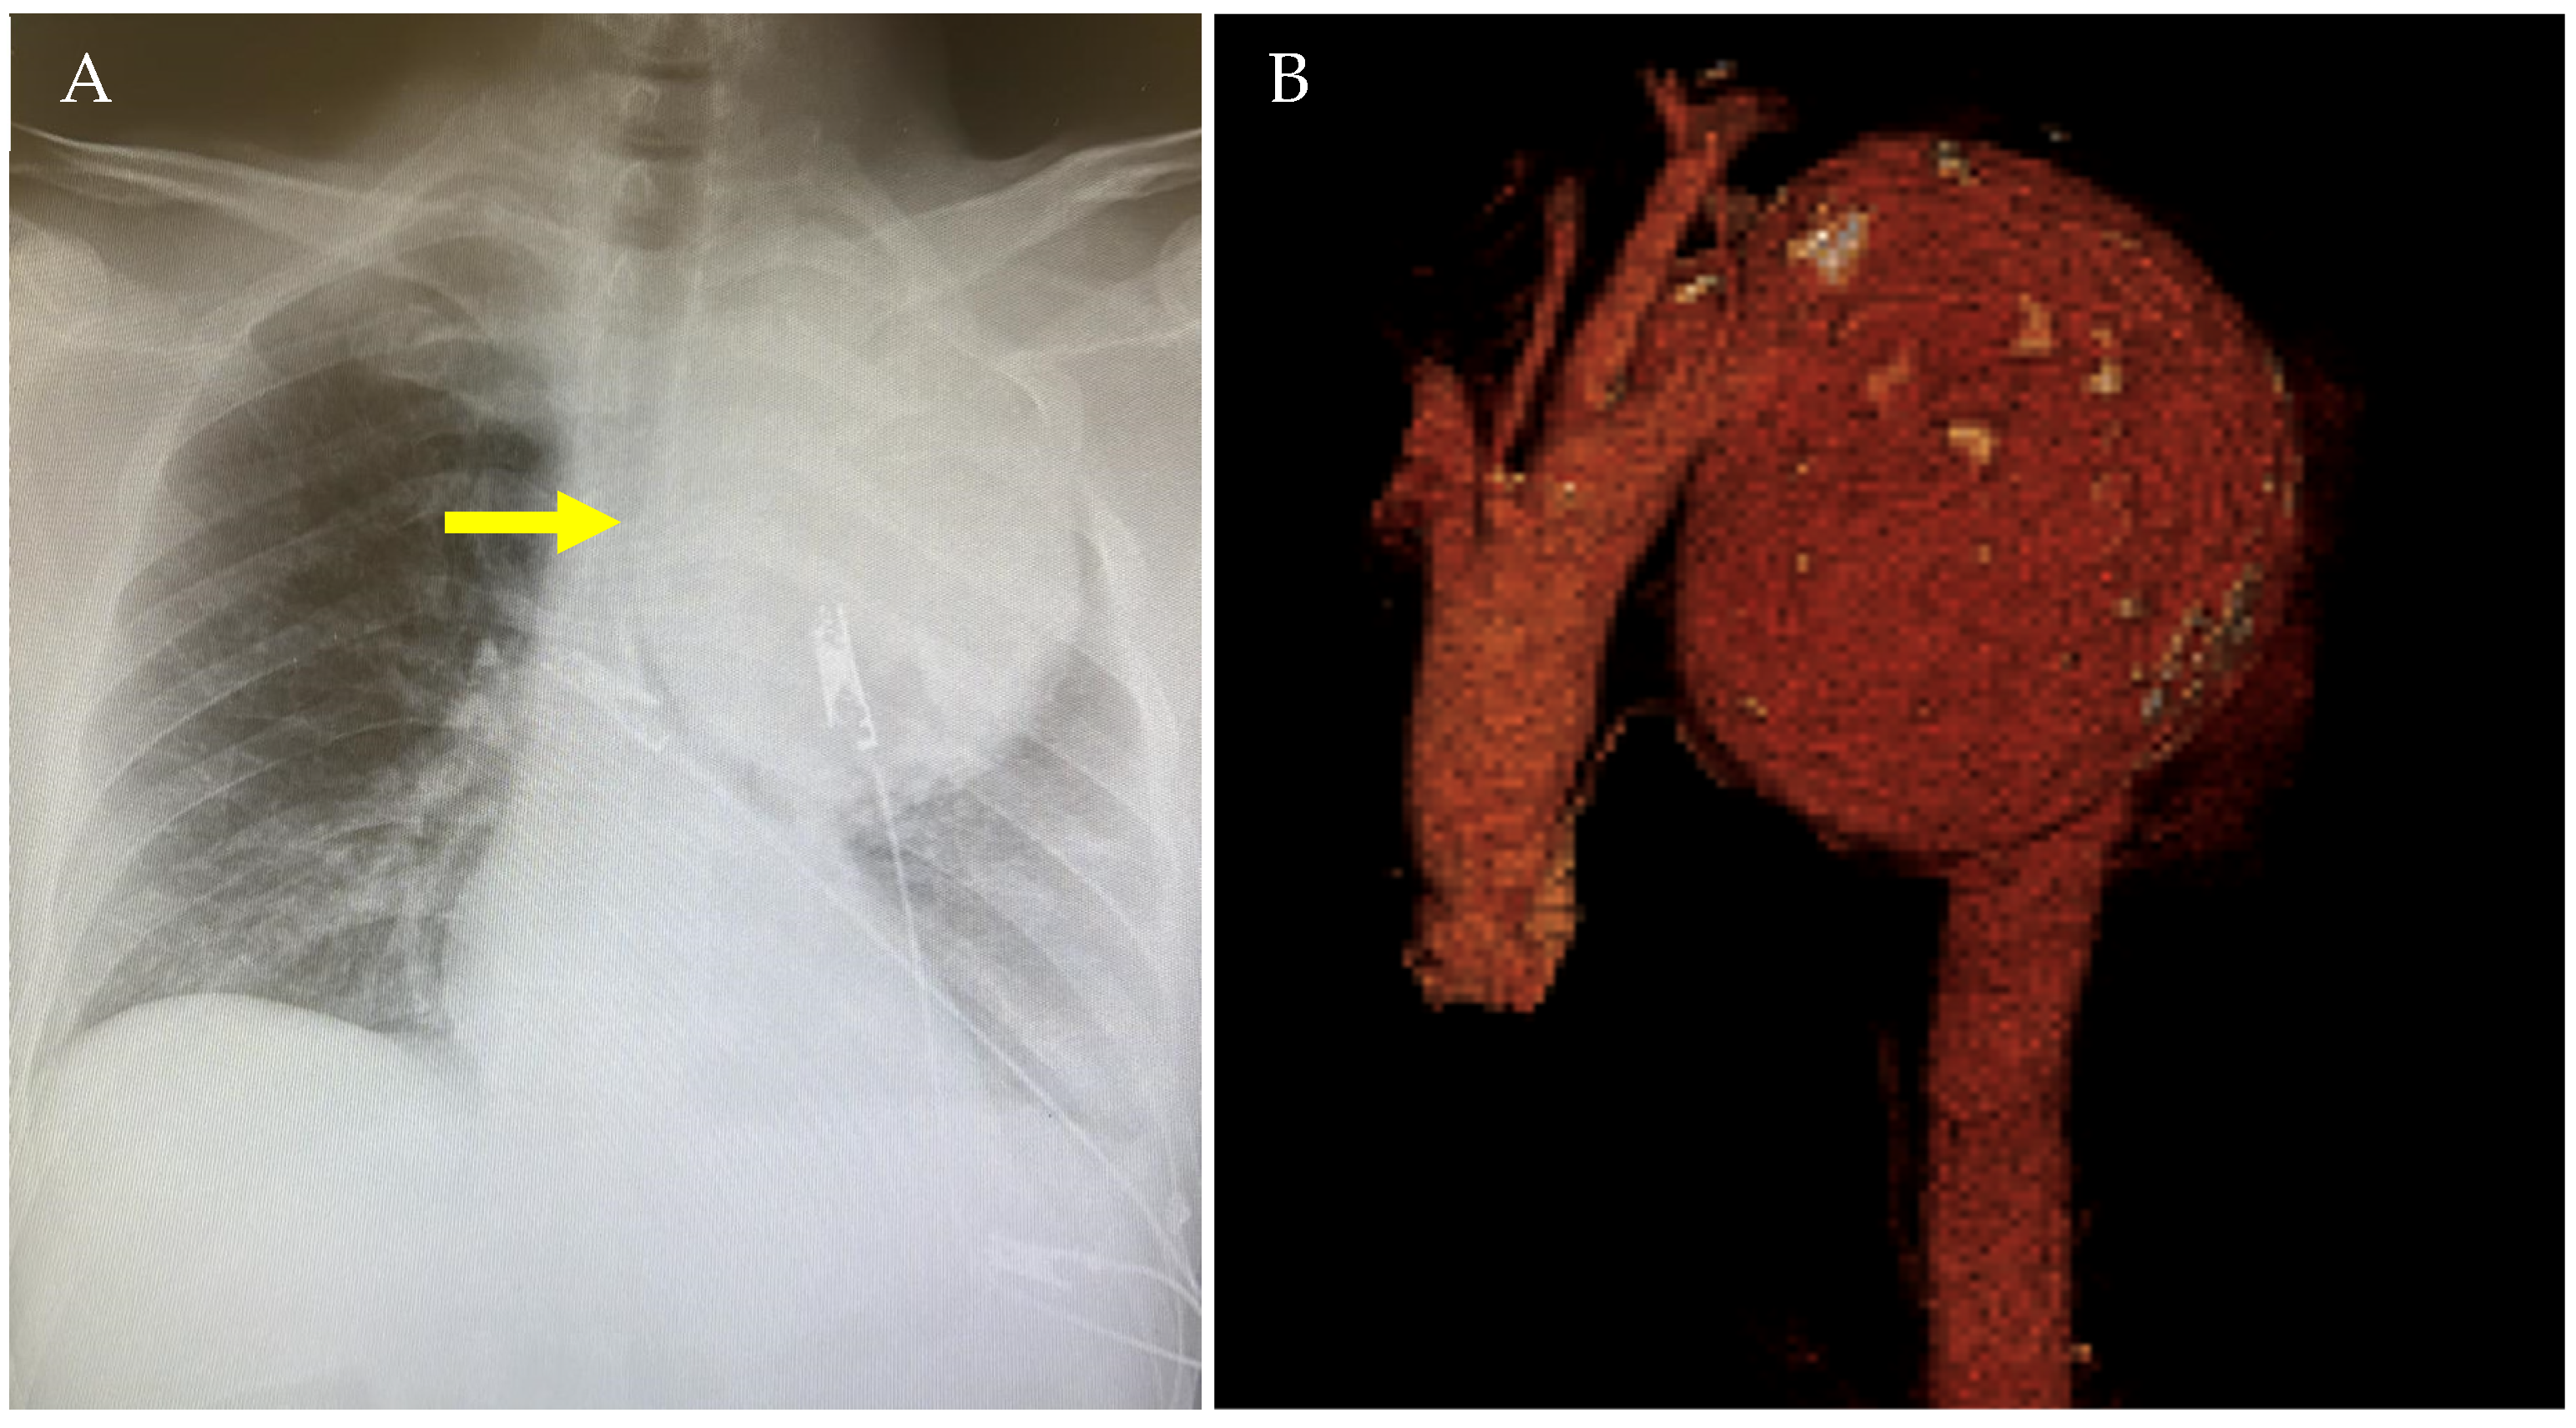

2.1. Case 1

| Current Case-1 | 48 | M | Aortic arch | Cough | 25 years | Hybrid (ET + TEVAR) |